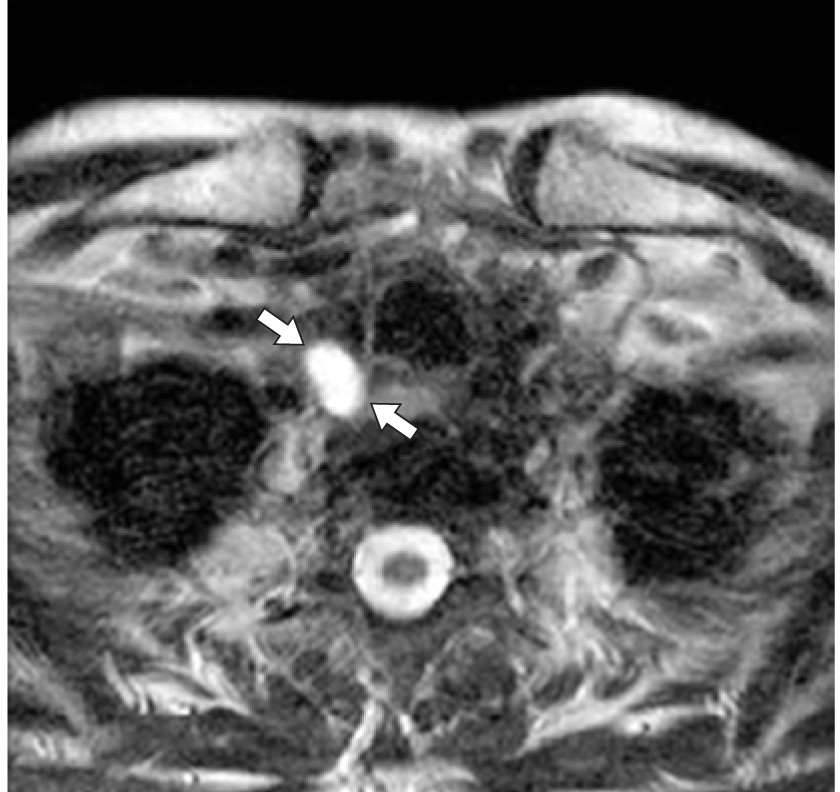

11. Fig. 10. Axial section of MRI in T2WI, an oval formation (arrows) was noted, which has a high signal intensity compared to the thyroid gland or lymph nodes (images from Diagnostic Imaging: head and neck, 3rd edition, Elsevier 2017). | |